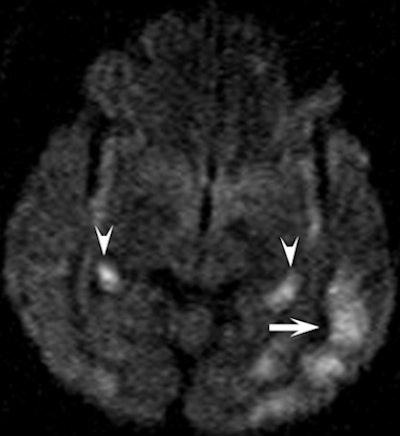

| Clinical images of a 51-year-old man found unconscious with a Glasgow Coma Scale score of 7 and withdrawal to pain. Above image shows fluid-attenuated inversion recovery, while below is a diffusion-weighted image that shows an increase in signal intensity in the head, body, and tail of the hippocampus bilaterally (arrowheads) and in the cerebral cortex (arrow). All images courtesy of Radiology and the National Neuroscience Institute. |

In a review of the images, the researchers found the hippocampus was affected bilaterally in seven patients, with variable involvement of the cortex in the parietal lobe (seven patients), temporal lobe (six patients), occipital lobe (five patients), and frontal lobe (five patients).

In seven patients, there was cortical involvement that the authors described as "patchy noncontiguous" in four cases and "confluent" in three patients, with sparing of the subcortical white matter and cerebellum. Three patients displayed abnormalities of the splenium of the corpus callosum in addition to the cortex.

"These findings are consistent with those of previous studies that described selective vulnerability of the brain to hypoglycemic damage and characteristic lesion distribution," the authors wrote.